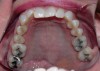

Generally with problems related to growth and development, such as bottle feeding, mouth breathing, tonsils, adenoids, and tongue thrusting,10 the maxilla shows a deep palatal vault and a V shape indicative of an unexpanded maxilla (Figure 1). All of these problems affect the maxilla, which then affects the way the mandible fits within its confines. This is similar to the maxilla acting as a "fence" or corral in which the mandibular teeth are the sheep. If the maxilla is constricted, then the mandibular teeth will crowd to accommodate to the space allowed by the maxillary teeth. The occlusal fencing concept is based on a structural maxillo-mandibular concept rather than a dental concept of occlusion. It takes into account 3-dimensional positioning in space.

Figure 1